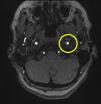

Based on the clinical presentation, the patient was diagnosed with a painful left-sided, partial Horner syndrome of unknown etiology based on the anisocoria and ptosis OS findings, however carotid artery dissection was highly suspected given the painful nature of presentation. Emergent imaging studies (including MRI/MRA, chest X-ray, and CT scans) were arranged through the PCP that same day. Four days later the PCP notified our clinic that the imaging studies had, indeed, revealed a carotid artery dissection of the distal half of the left internal carotid artery (ICA) at the level of approximately cervical vertebrae C3. Figs. 2–4 highlight the dissection of1 the left internal carotid artery via standard MRI and MRA which was classified as “severe” by the radiologist and scored as an “8 or 9 on a scale to 10”. The PCP had urgently started the patient on 325mg of aspirin daily and referred the patient to a neurologist for further consultation.